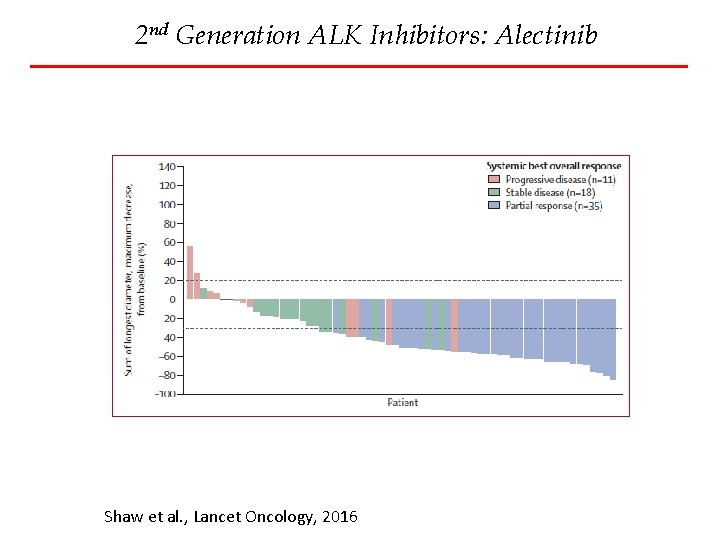

2 nd Generation ALK Inhibitors: Alectinib Shaw et al. , Lancet Oncology, 2016